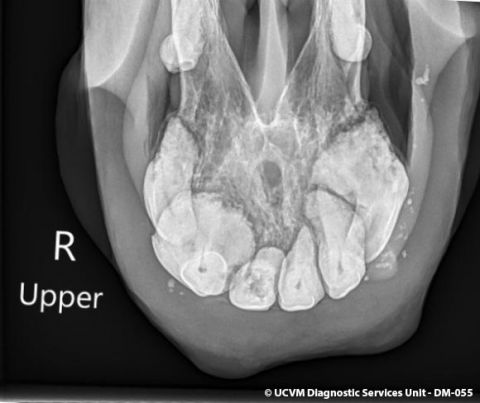

Species: Equid, Horse

Specimen: Teeth

Shown: EOTRH equine odontoclastic tooth resorption and hypercementosis